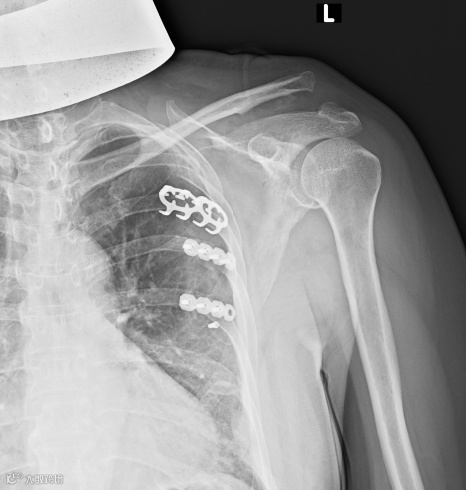

(传统手术,创口大)

带袢钢板微创内固定术

术后(伤口小)

与传统钩钢板手术相比,带袢钢板微创治疗肩锁关节脱位的主要优势有:

(1)手术创伤小,术后恢复快;

(2)无须二次手术取出内固定物,减少患者的痛苦和治疗费用;

(3)使用带袢钢板,在固定肩锁关节的同时重建喙锁韧带,符合肩锁关节的生物力学环境;

(4)不会发生内固定物断裂,不会对肩袖产生干扰,减少了肩关节疼痛的风险,减少肩峰撞击;

(5)减少了内固定物取出后复位丢失的发生率。

带袢钢板是在锁骨和喙突间再一次建立了喙锁韧带相似的解剖构造(相当于为患者重建一条“韧带”),在纵、横向两个方向都起到了坚强的稳定作用,且重建的结构大于喙锁韧带的强度,具备较好的稳定性及疗效。

所以此种手术方式,有手术时间短、术中出血少、创伤小、住院时间短及费用少、术后肩关节功能良好等优点,较锁骨钩钢板而言具有一定优势。